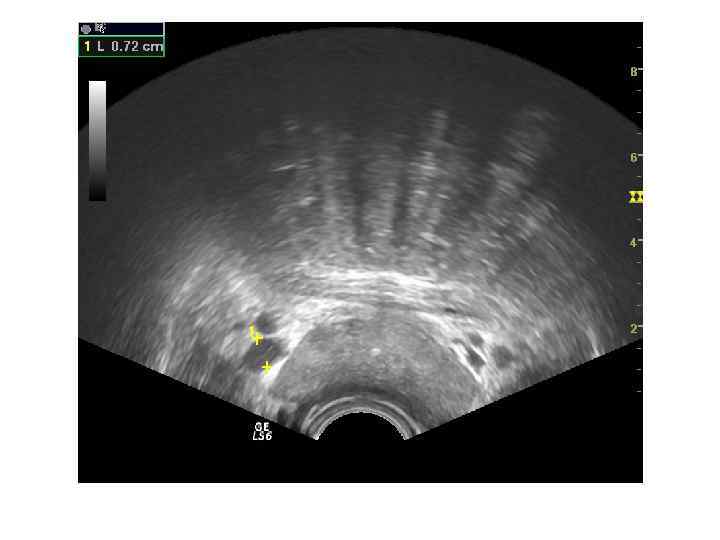

Производится ТРУЗИ простаты. При продольном сканировании выбирается место биопсии, используется направитель иглы на экране аппарата. Образцы ткани берутся примерно на половине расстояния между уретрой и боковой поверхностью железы, из основания, средней части и верхушки обеих сторон простаты. Биопсийная игла вводится через стенку прямой кишки до капсулы железы, затем выстреливается и удаляется. Образцы ткани помещаются в раздельные емкости с фиксирующим раствором и помечаются.